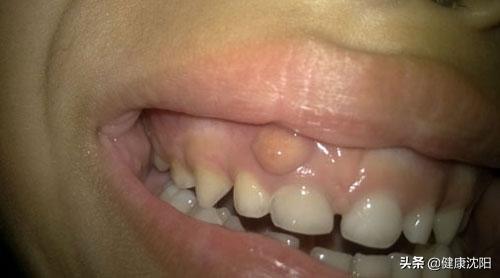

牙龈上长脓包,就是老百姓说的牙宣,类似这样的情况,相信大家在日常生活中,已经亲身感受过了,或者听周围的人提起过了。很多患者起了牙龈脓包,特别害怕,以为是牙龈癌。那么,牙龈脓包到底怎么回事?为什么脓包会“反反复复”,究竟是什么原因呢?下面给大家科普一下。

在日常生活中,之所以会出现牙龈上反复长脓包的情况,大多数是因为得了一种叫做“慢性根尖周炎”的牙齿疾病,是牙齿根尖周围组织发炎引起的。分析其原因,很可能是因为龋病、牙外伤、牙髓炎等牙齿问题没有得到及时治疗,或者是既往牙髓治疗不完善,导致牙根根尖周围的牙槽骨慢性进行性破坏。慢性根尖周炎通常没有明显的自觉症状,患者可在咀嚼时有不适感,通常是以牙龈脓包为主诉就诊。因为在日常生活中,大家经常以“牙痛”来衡量牙齿是否有问题,如果牙齿不出现疼痛,大家就以为牙齿没有问题了,或者认为牙痛好了。其实坏死的牙髓里的细菌仍然在繁殖,炎症通过根管及根尖端慢慢向牙槽骨里蔓延。长此以往牙龈上就长了脓包。